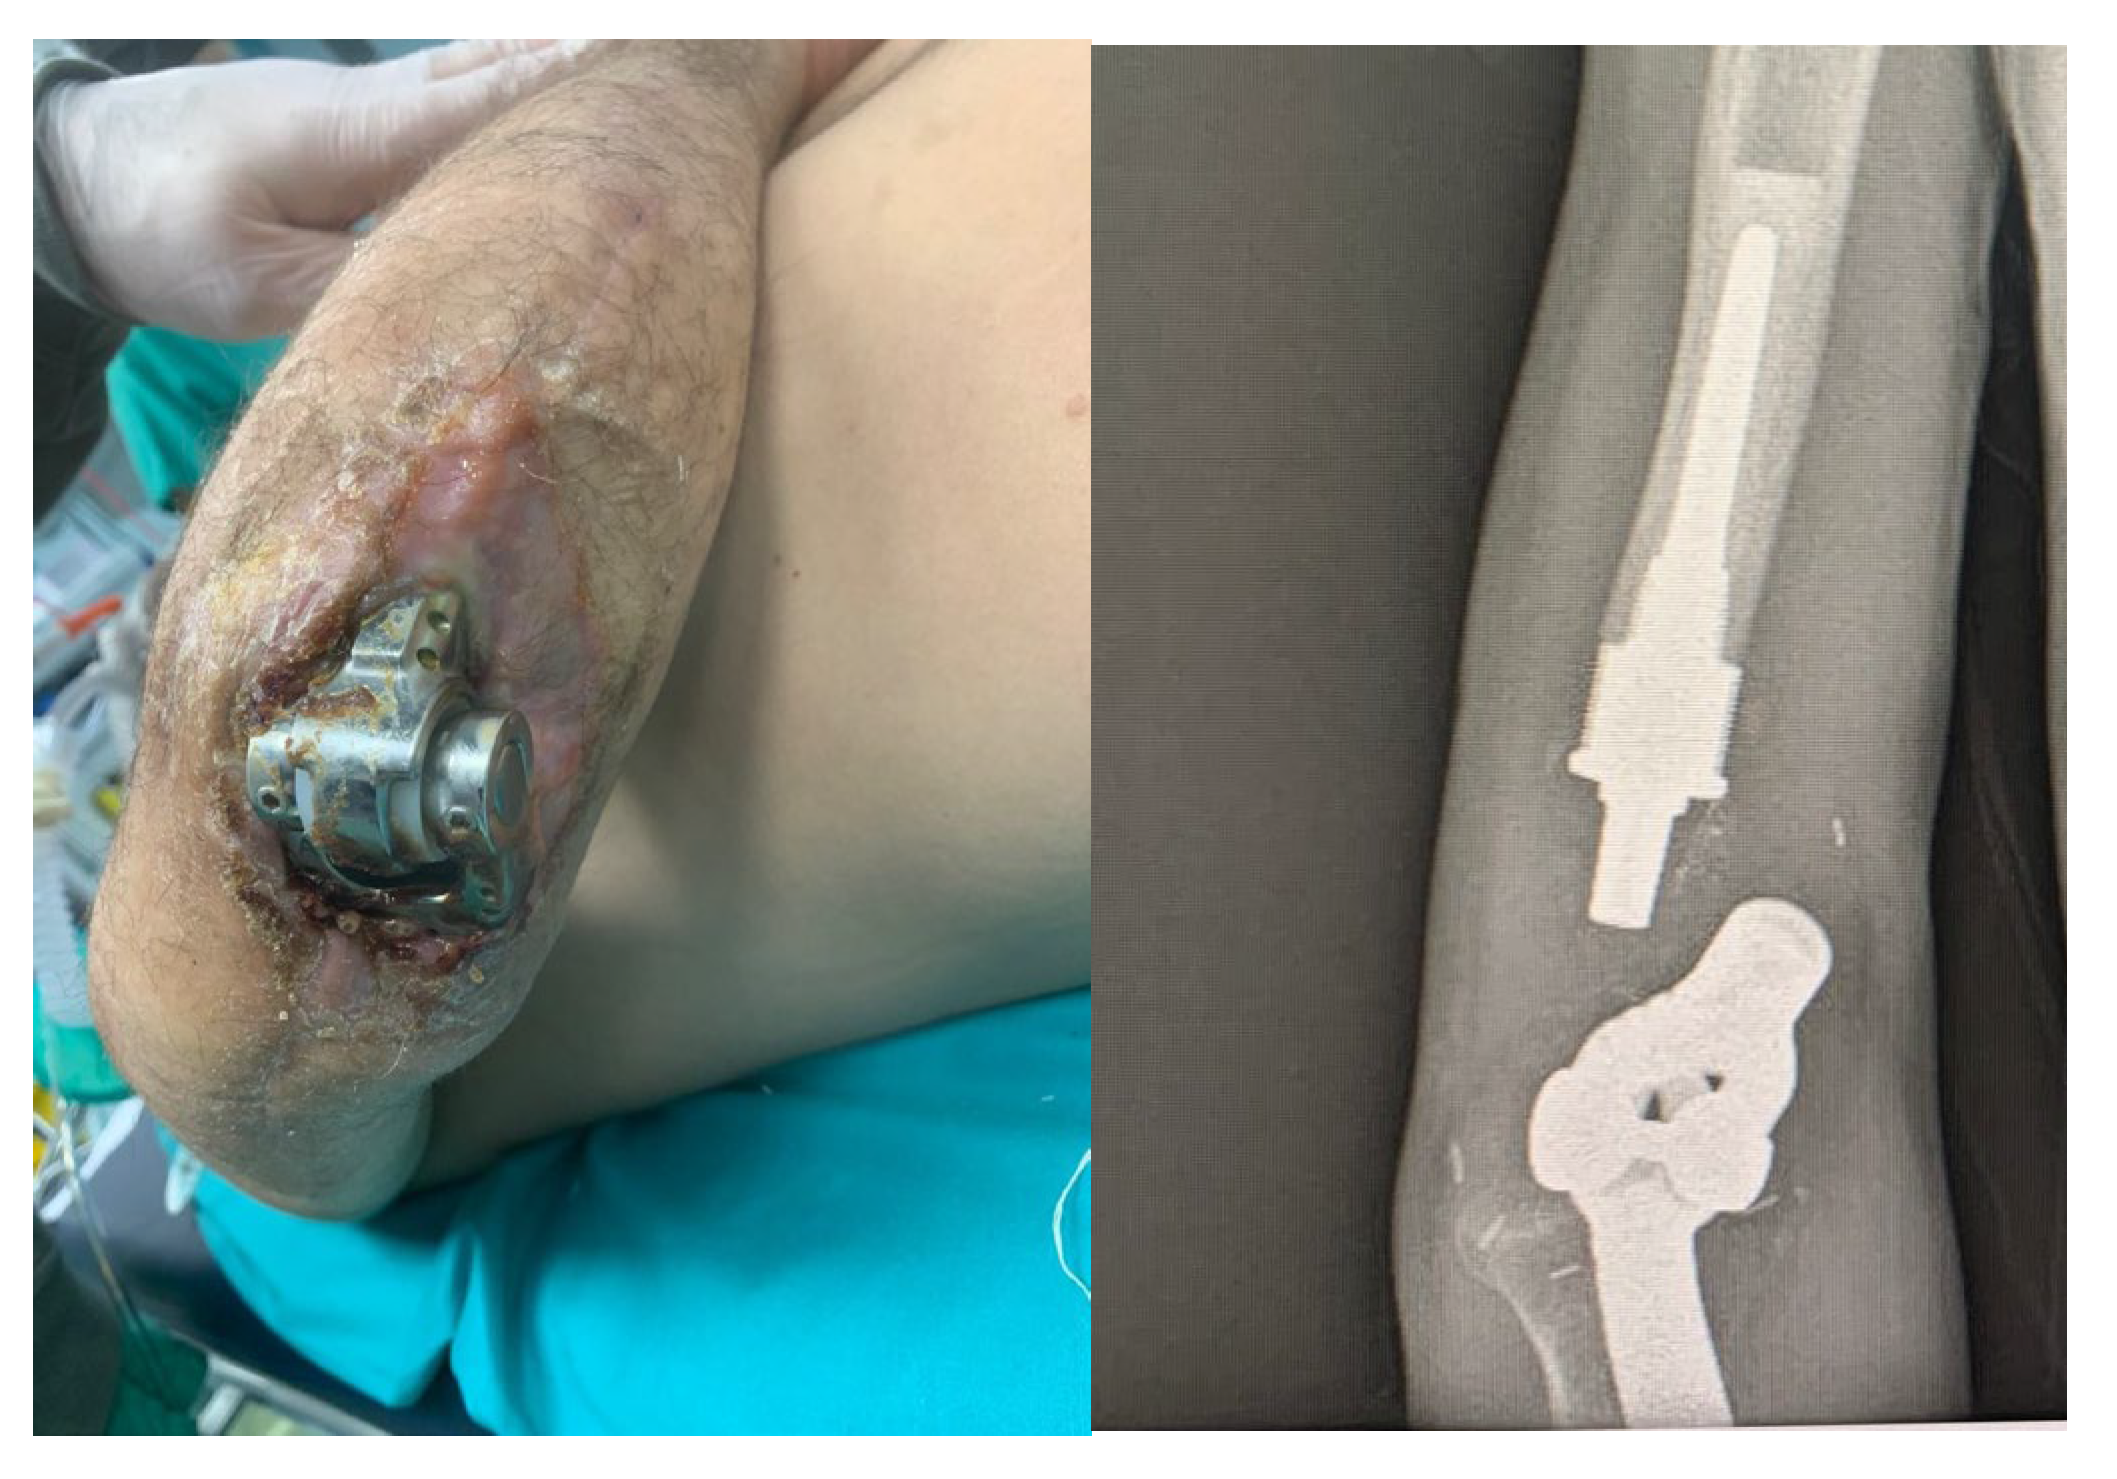

4.2. Case 2: Complex Open Fracture of the Elbow